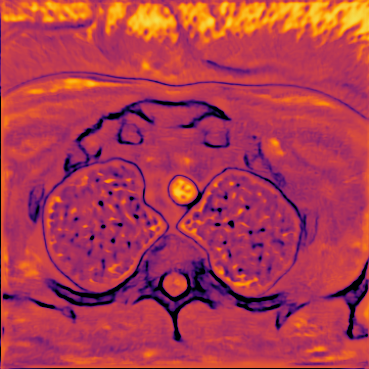

Figure 6 shows examples of the quantitative (magnitude) images of three of the 112 simulated inversion recovery measurements in the test dataset. We also show the regularization parameter-maps for regularization along the spatial directions and along the inversion-time direction generated by the network. The mean PSNR and SSIM of our proposed method is consistently higher for all considered acceleration factors, even compared to PDHG with regularization strength along spatial and inversion-time direction chosen by grid-search with access to the ground truth images (shown in Figure 8 and Table 2). The resulting parameter-maps after performing the regression on the reconstructed images are shown in Figure 7. Again, our proposed method results in the lowest RMS deviation from the ground truth images (Table 2).

We compare the 2D time frames of the video samples from the test dataset to the denoised frames, regularized by , and by the spatio-temporal parameter-map . The metrics were calculated frame-wise for all samples at three different noise levels, characterized by the standard deviation of the Gaussian distribution. From the box-plots in Figure 10 we see that the PDHG reconstructions using the proposed spatio-temporal regularization parameter-map yield superior reconstructions compared to and with respect to all measures.Table 3 quantitatively summarizes the results . In Figure 9, we compare two samples from the test dataset with a static camera view in the first row and a dynamic camera view in the third row. The vertical red lines in Figure 9 indicate the -location of the -excerpt shown to the left of each image. The second and the fourth row show the pointwise absolute errors of the respective images. For both samples, the lowest error is achieved by the parameter-map. The spatial and the temporal components of the obtained regularization parameter-maps are visualized in Figure 11. Here, the noisy samples, the results obtained with PDGH using , the spatially and temporally dependent parameter-maps and the ground truth-images are depicted. By comparing the static and dynamic case, we see that the trained CNN is able to differentiate between the two inherently different cases. Thereby, for the video sample with the static camera position, where the background remains constant over time and only objects are changing position, the CNN imposes an overall higher temporal regularization. For the video sample where the camera position also changes over time, the CNN is able to predict the less prominent potential to exploit the temporal gradient-sparsity and thus assigns relatively low